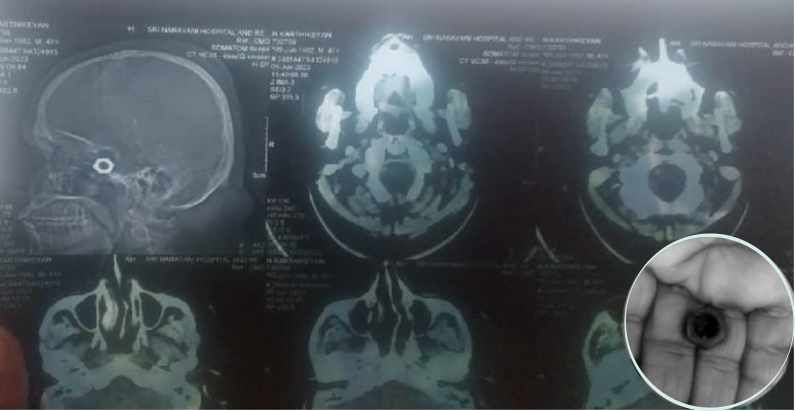

تاہم زخم سے خون بہنا بند نہ ہونے پر اہل خانہ کو شک ہوا اور اسے نجی اسپتال لے گئے۔ ڈاکٹروں نے وہاں اسکین کیا تو اصل بات سامنے آئی۔ سر پر جہاں ٹانکے لگائے گئے تھے وہاں لوہے کی نٹ دیکھ کر ڈاکٹر حیران رہ گئے۔اسکین میں ڈاکٹروں کو کارتیکیان کے سر میں لوہے کا نٹ ملا۔ بعد میں آپریشن کیا گیا اور آئرن نٹ نکال دیا گیا۔